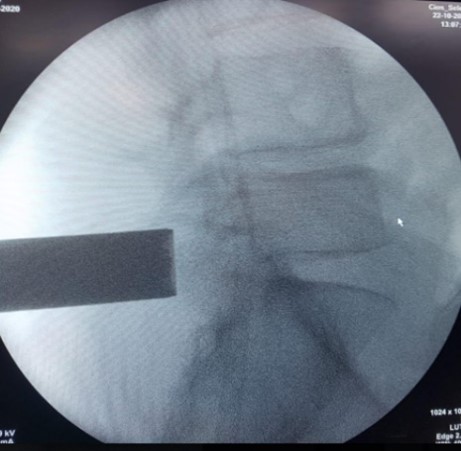

Procedimientos percutáneos de diversa índole: biopsias percutáneas para diagnosticar tumores o infecciones, cifoplastia o vertebroplastia para tratar fracturas por osteoporosis.